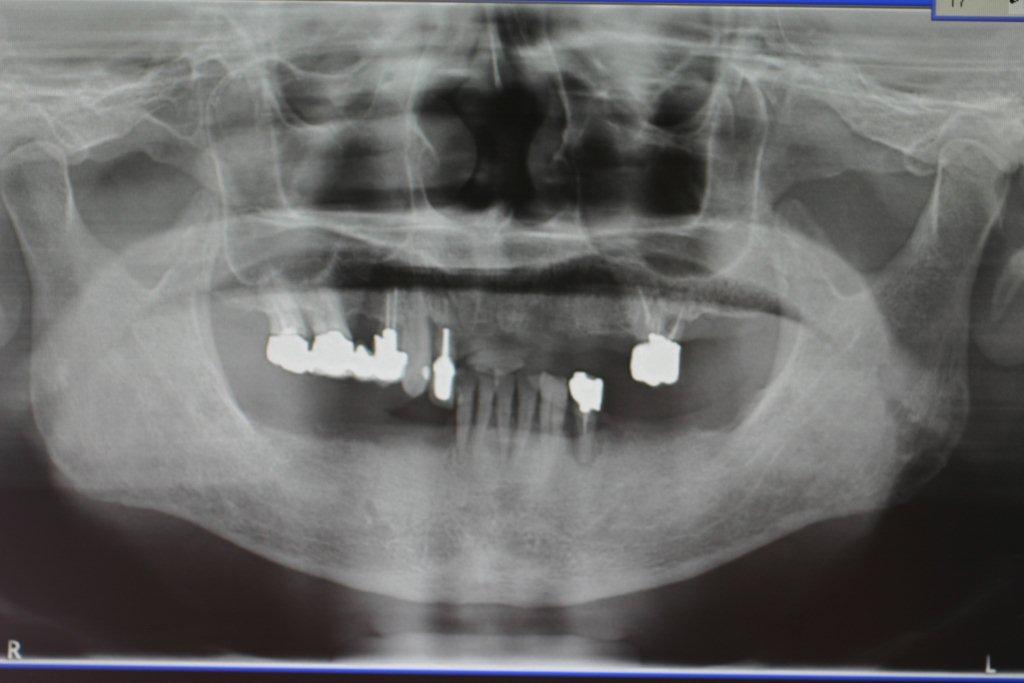

上・下多数の歯が欠損しているケースです。

1本の歯に対して、1本のインプラントで治したいという 患者様の希望により、上6本、下9本、合計15本のインプラントを 埋入し治療したケースです。